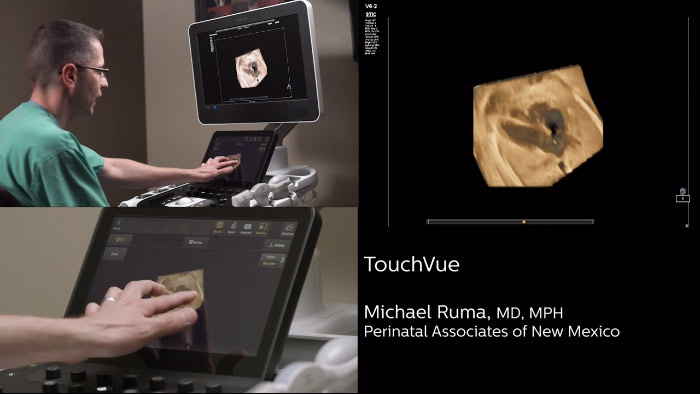

Philips TrueVue, TouchVue, GlassVue, aReveal

En este vídeo, el Dr. Michael Ruma, de Perinatal Associates, Nuevo México (EE. UU.), explora el uso de TrueVue, TouchVue, GlassVue y aReveal de Philips para exploraciones de obstetricia/ginecología.